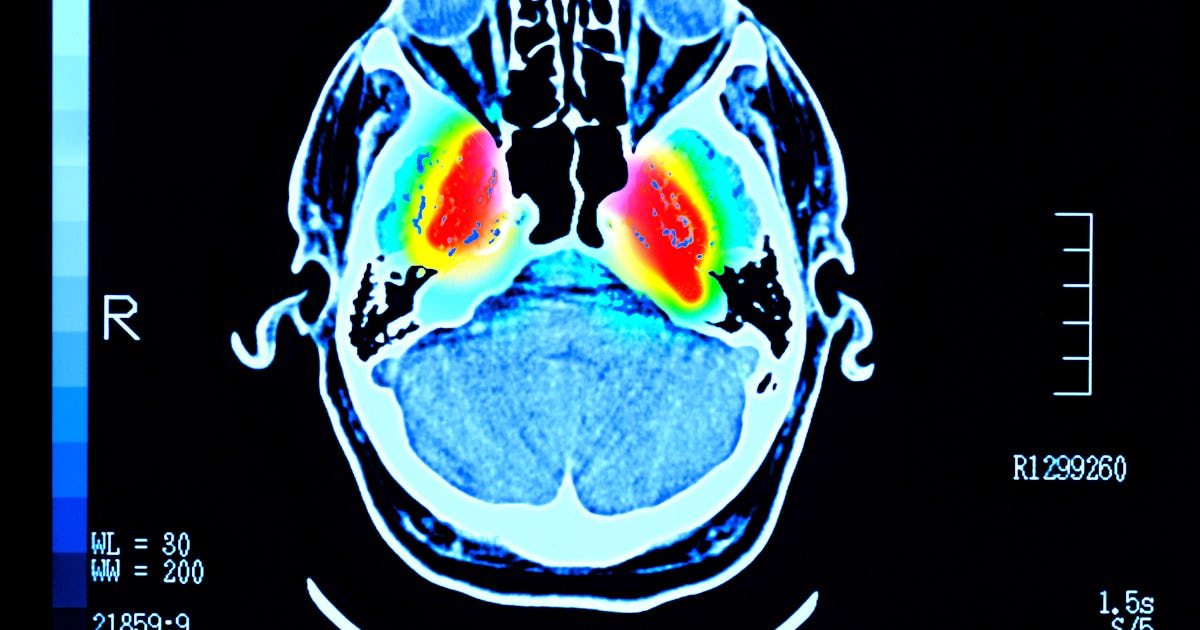

The olfactory system is constantly bombarded with odors, pollutants, and pathogens. Particles inhaled through the nostrils bind to specific olfactory receptor cells in the tissue lining the nasal cavity. These receptors send messages to other cells in what's called the olfactory bulb, which acts like a relay station that transmits these messages down the long nerves of the olfactory tract. These messages are then transferred to the area of the brain responsible for learning and memory, the hippocampus.

The hippocampus plays a critical role in assigning contextual information to odors, such as danger from the foul smell of propane or comfort from the smell of lavender. This area of the brain is also dramatically damaged in Alzheimer's disease, causing devastating learning and memory deficits. For as many as 85 to 90 percent of Alzheimer's patients, loss of smell is an early sign of disease.